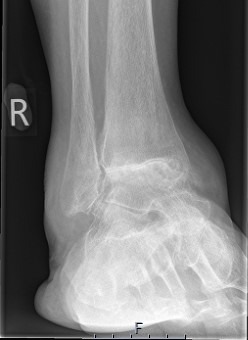

Ankle Arthritis

Total Ankle Replacement

Arthroscopic surgery of the ankle and hindfoot